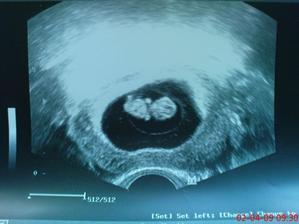

* 4.3.2009 první kontrola, bublinka měří neuvěřitelný centimetr a zabydleli jsme se tam kam patříme 🙂 potvrzen 4tt